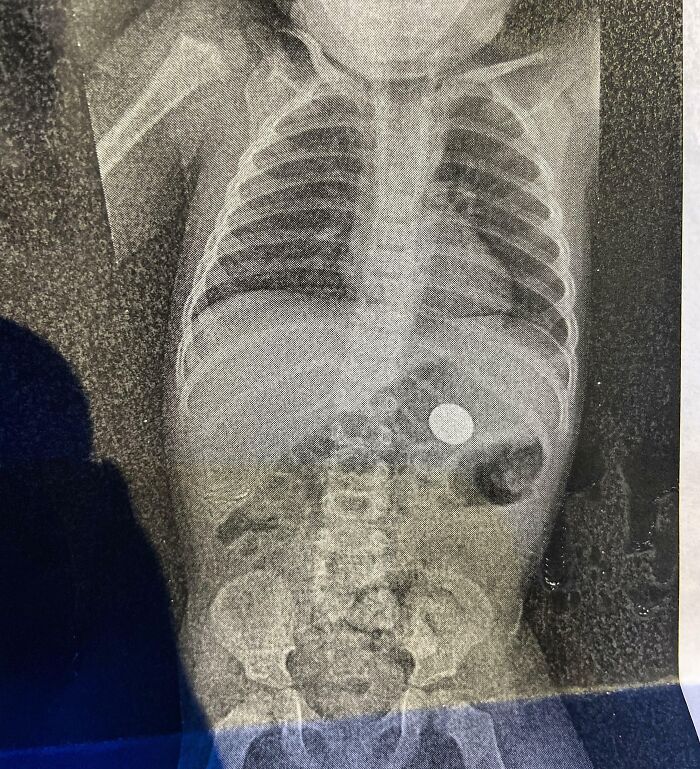

#5 On Valentine's Day, My Son Decided To Show Me His First Magic Trick: How To Make A Coin Disappear. One X-Ray Later, I Found It

Image credits: Ordinary-Possession4